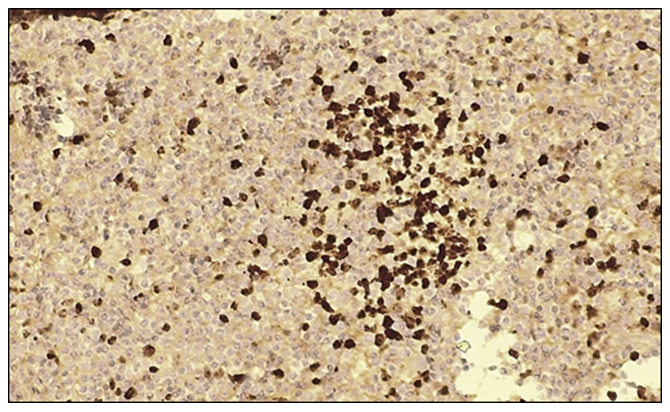

In large cell carcinoma of the lung, CD34 marker expression was evaluated to assess tumor vascularity and its association with metastatic potential. The results were interpreted as negative or positive reactions. A positive CD34 reaction was observed in all 20 patients (100%), characterized by distinct staining of endothelial cells lining the vessel walls. This finding facilitated the assessment of microvessel density in the present study, with several blood vessels clearly visualized per high-power field (objective ×10, ocular ×40). The pronounced vascularization of the tumor tissue indicates high angiogenic activity, suggesting an increased metastatic potential of the tumor.Microscopically, tumor cells with large-cell epithelial differentiation exhibited marked polymorphism, hyperchromatic nuclei, and numerous pathological mitotic figures. The epithelial stroma contained angiomatous blood vessels with intensely dark-brown–stained walls. A high microvessel density of approximately 30–40 or more blood vessels per field of view was identified. | Figure 8. Negative CD34 immunohistochemical reaction in large cell carcinoma of the lung. IHC, DAB chromogen. Objective ×10, ocular ×40 |